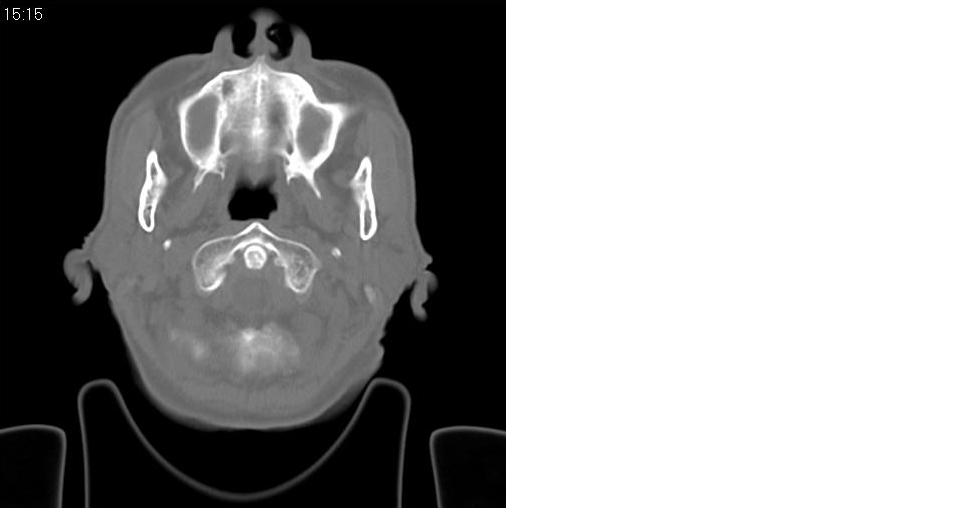

以下是引用zrs在2009-4-21 18:22:00的发言:[br]左侧额窦、筛窦及上颌窦内均充以软组织密度影,且窦壁骨质明显增厚,右侧上颌窦粘膜环形增厚。左侧鼻腔内亦见软组织密度影。考虑慢性鼻窦炎。

以下是引用hnfsh在2009-4-21 19:56:00的发言:[br]病灶主体位于左侧鼻腔内,呈膨胀性生长,鼻中隔、左侧筛板骨质吸收破坏,双侧上颌窦、额窦内聪充满软组织密度影。 考虑:1。左侧鼻息肉 2。慢支副鼻窦炎

以下是引用张xyz在2009-4-21 20:59:00的发言:[br]全组副鼻窦炎并息肉样变[br]